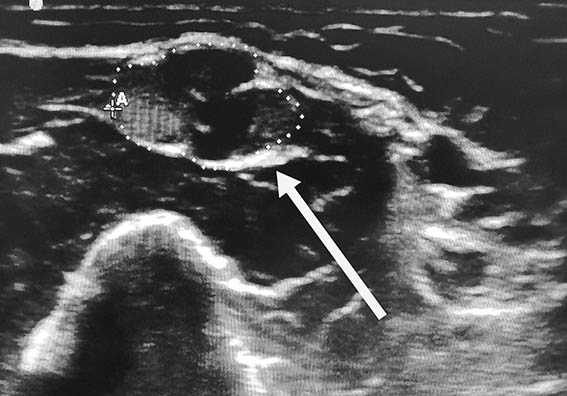

Игольчатая электромиография

При игольчатой электромиографии регистрируется активность первой дорзальной межкостной мышцы (локтевой нерв) в ответ на сопротивление во время произвольного мышечного сокращения. Могут иметь место следующие нейрофизиологические признаки нейропатических расстройств:

- Сниженные чувствительные и двигательные потенциалы - говорят о нефункционирующих нервах;

- Отсутствие чувствительного ответа - отражает нарушение дальше межпозвонкового отверстия (в сплетении);

- Неизменный чувствительный ответ при гиперстезии конечности говорит о патологических изменениях выше межпозвонкового отверстия (пролапсе диска);

- Блок проведения - наличие дистального двигательного ответа с локальным блоком проведения указывает на нейропраксическое обратимое повреждение.

Денервационные изменения на электромиограмме более чем через 10 дней после травмы верхней конечности подтверждают существенное повреждение нерва и потерю им проведения двигательных импульсов. Наличие любого количества произвольно функционирующих двигательных единиц в слабой руке свидетельствуют о возможности восстановления.